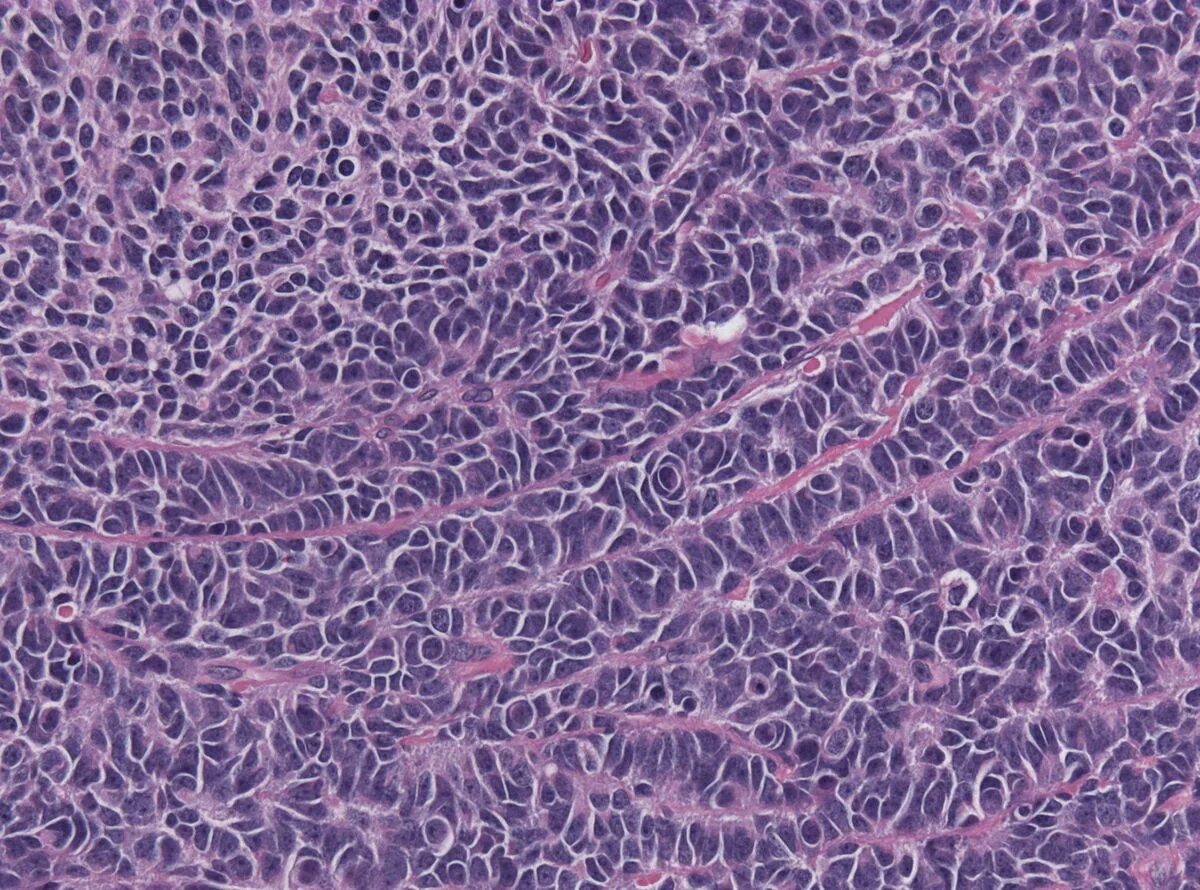

Медуллобластома это